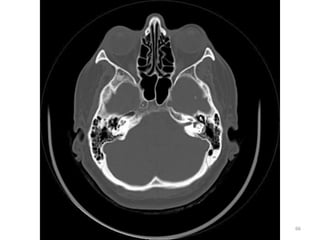

1. Cristalino do olho D.

2. Lobo parietal E.

3. Medula Oblonga

(bulbo).

4. Seio esfenoidal.

5. Corpo vítrio (globo

ocular).

6. Hemisfério cerebelar D

34

1. Músculo reto medial D.

2. Músculo reto lateral E.

35